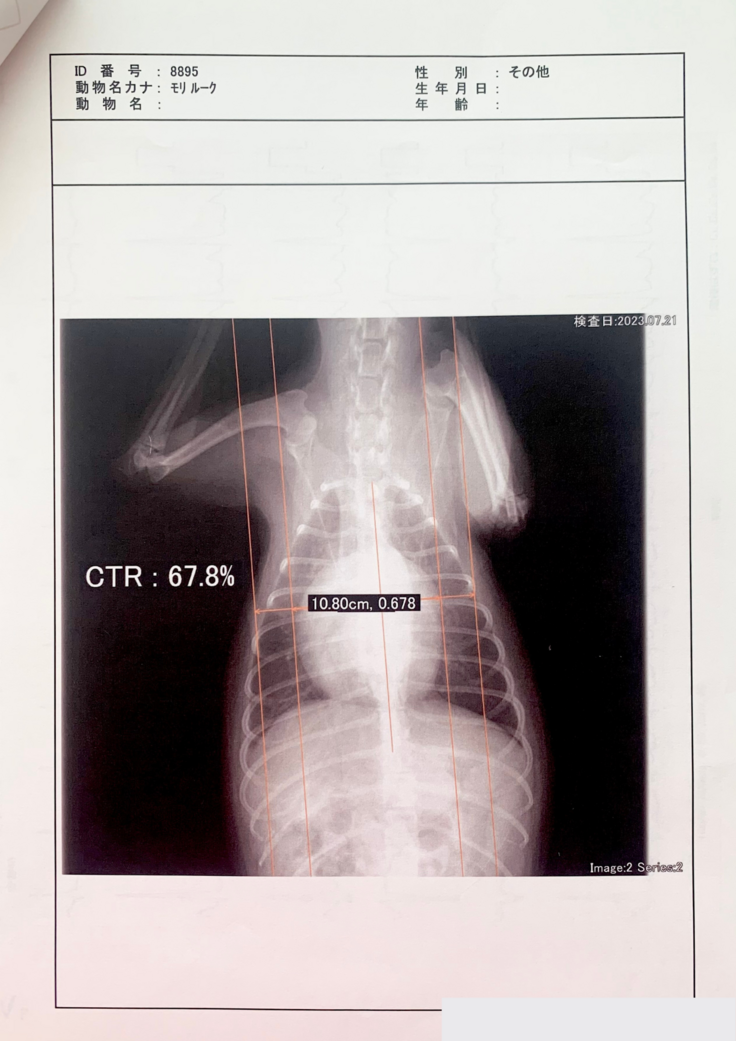

度々の咳が続き、気になり検査したところ、2023年の1月に、「僧帽弁閉鎖不全症」という病気だったということが分かりました。

僧帽弁とは、左側の左心房と左心室の間にある弁のことです。通僧帽弁の働きにより左心房から左心室への一方向にしか血液は流れませんが、僧帽弁閉鎖不全症では、弁がうまく閉まらなくなることで逆方向の血流が認められるようになります。心臓が大きくなると、心臓だけでなく肺にも血液が溜まり、肺水腫と呼ばれる状態になります。

手術でしか治るものはなく、それをしなければ薬で延命治療をするというものです。

その後2月、4月、7月に病院に行っています。

最終的に肺水腫と気管虚脱も発症しており、

かなりの重症でした。